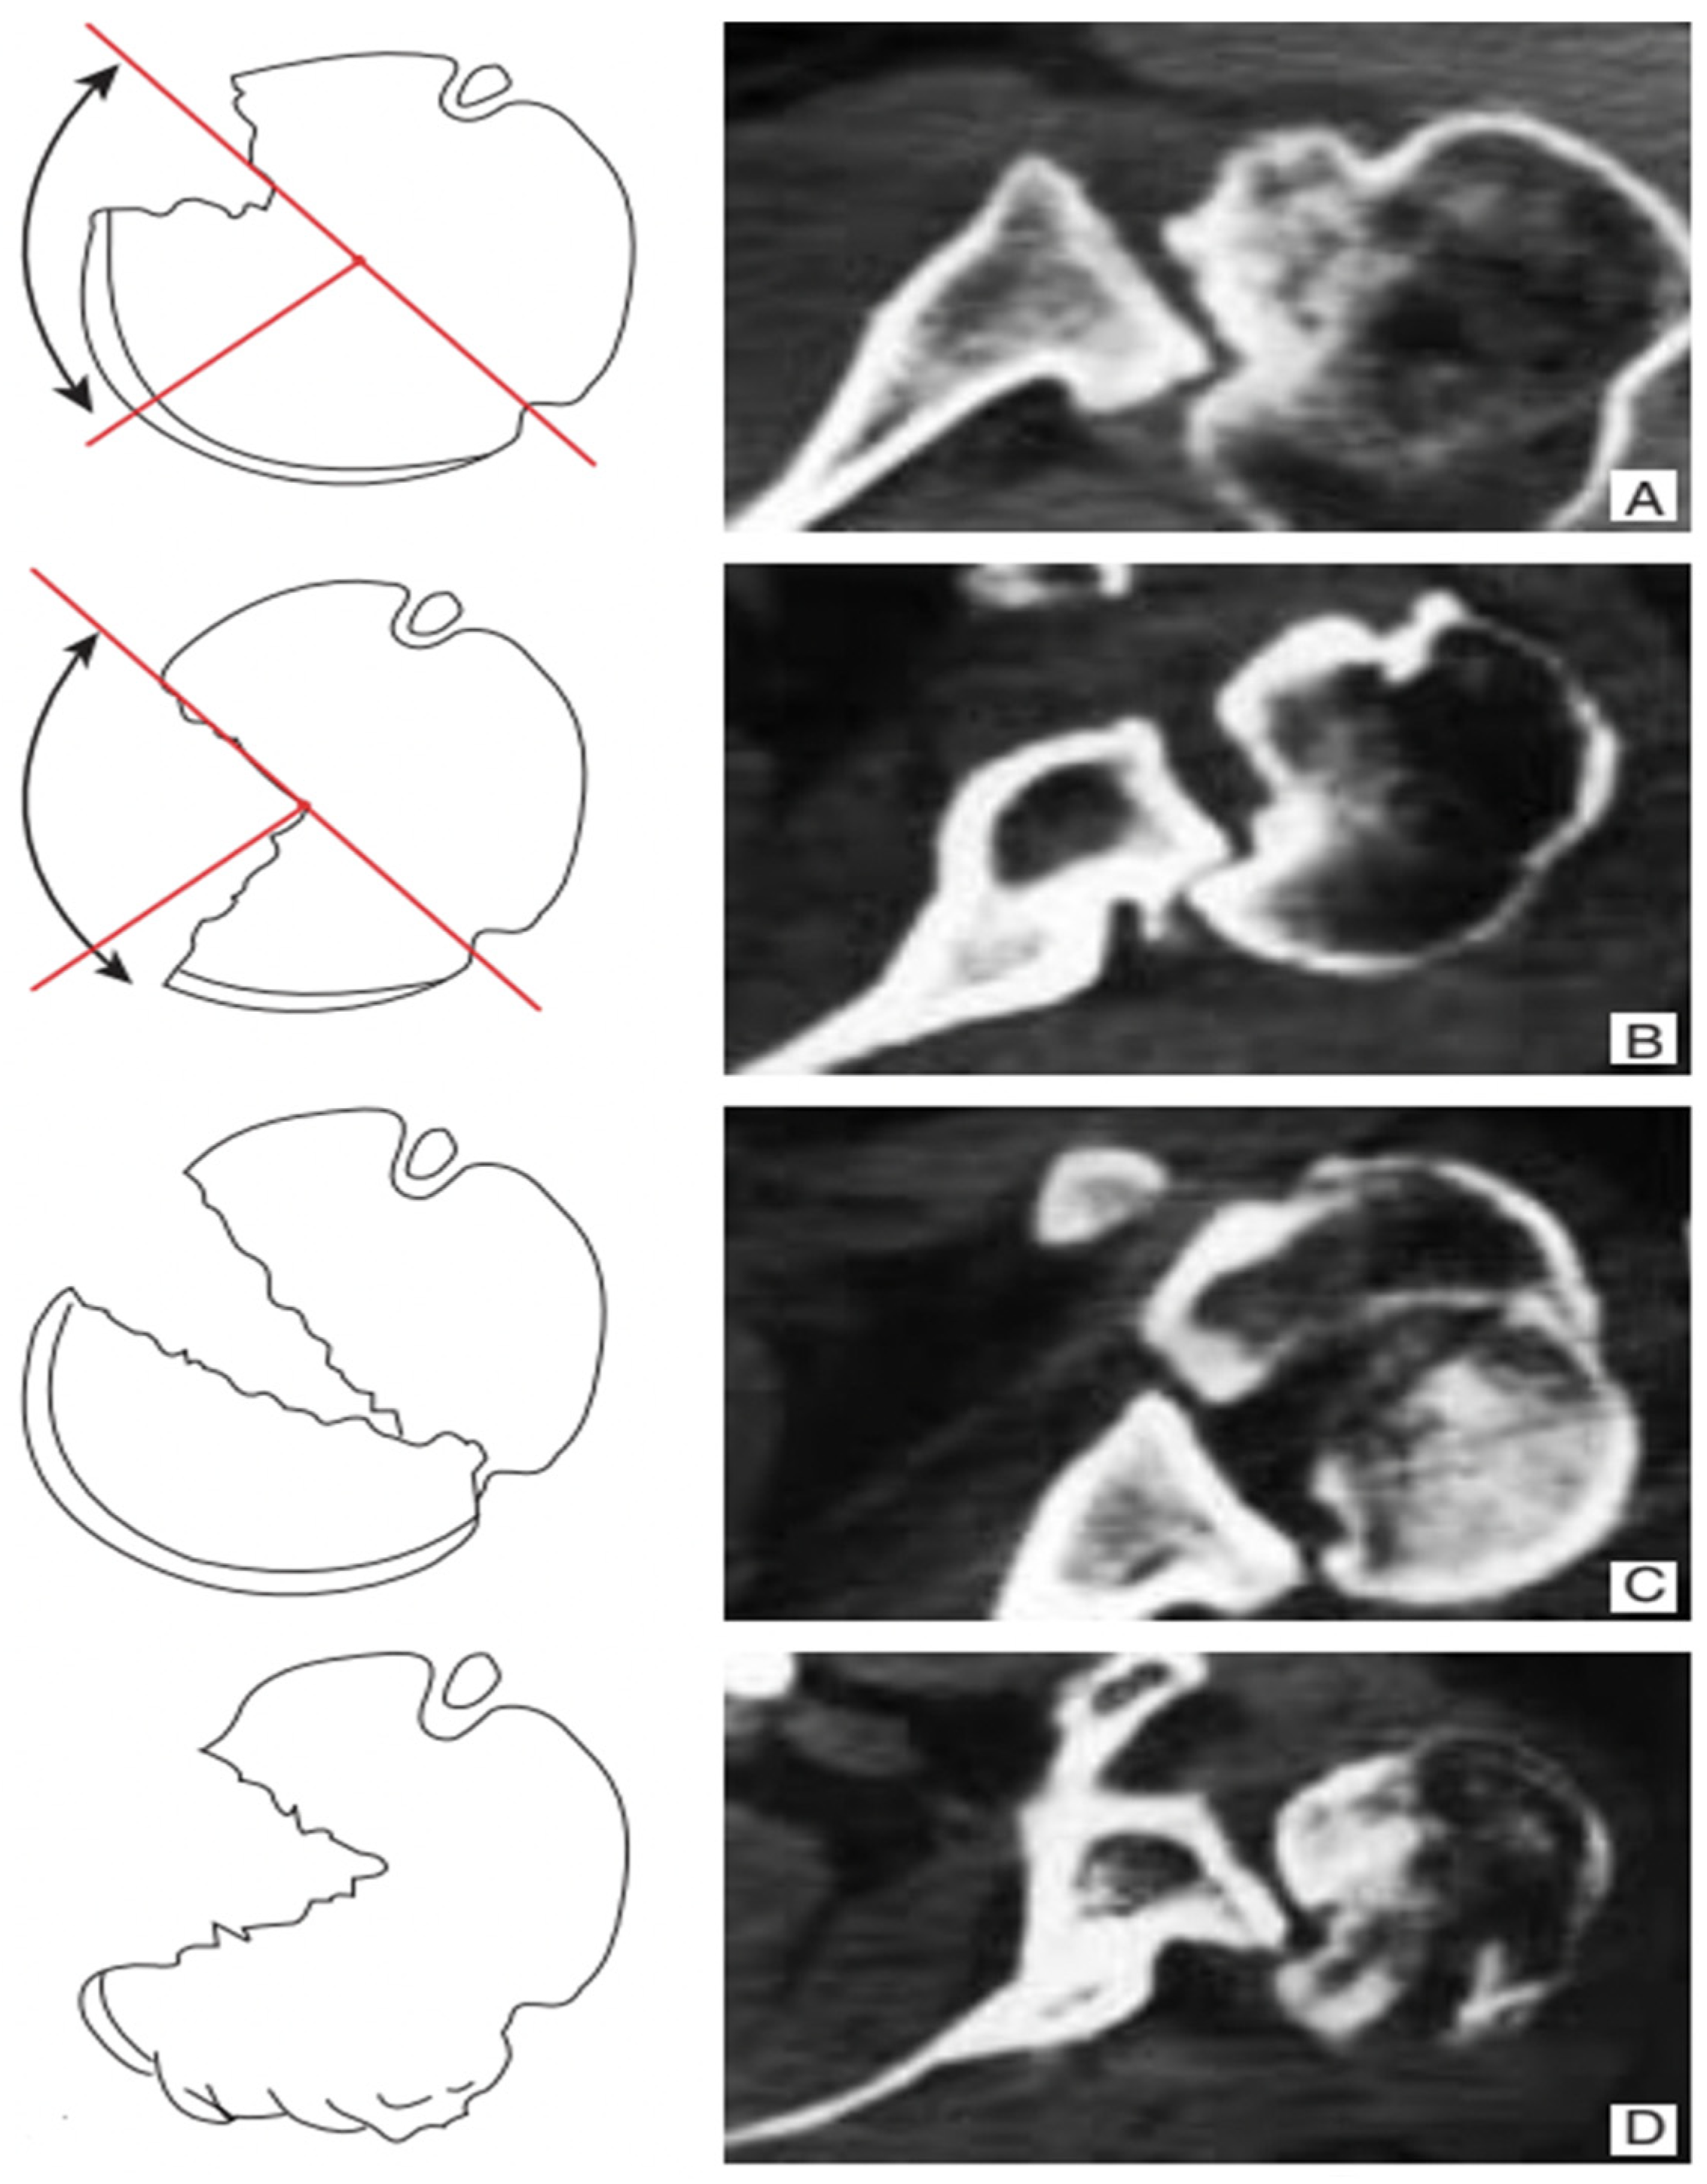

We therefore have the following four types of confirmed posterior fracture dislocation (Figure 1):

Type 1: chronic posterior dislocation is associated with humeral bone deficit ranging from 20% to 50% of the extension of the articular surface; it is the most frequent type;

Type 2: the deficit is greater than 50%;

Type 3: fracture dislocation of the humeral head, in which the continuity between the humeral head and the diaphysis is ensured by a posterior bony portion which acts as a hinge between the two structures. The fracture can be localized at the anatomical neck level, or it can involve a medial portion of the diaphysis. The articular pro-file of the humeral head is preserved.

Type 4: the fracture is multi-fragmentary with complete subversion of the profile of the articular surface [4].

Figure 1. Classification of chronic posterior shoulder dislocation and fracture dislocation. Type 1 (A) humeral bone deficiency extending from 20 to 50% of the articular surface of the humeral head; Type 2 (B) humeral bone deficiency extending to more than 50% of the articular surface of the humeral head; Type 3 (C) fracture dislocation of the humeral head in the absence of bone deficiency. Type 4 (D) fracture dislocation with multifragmentation of the humeral head.